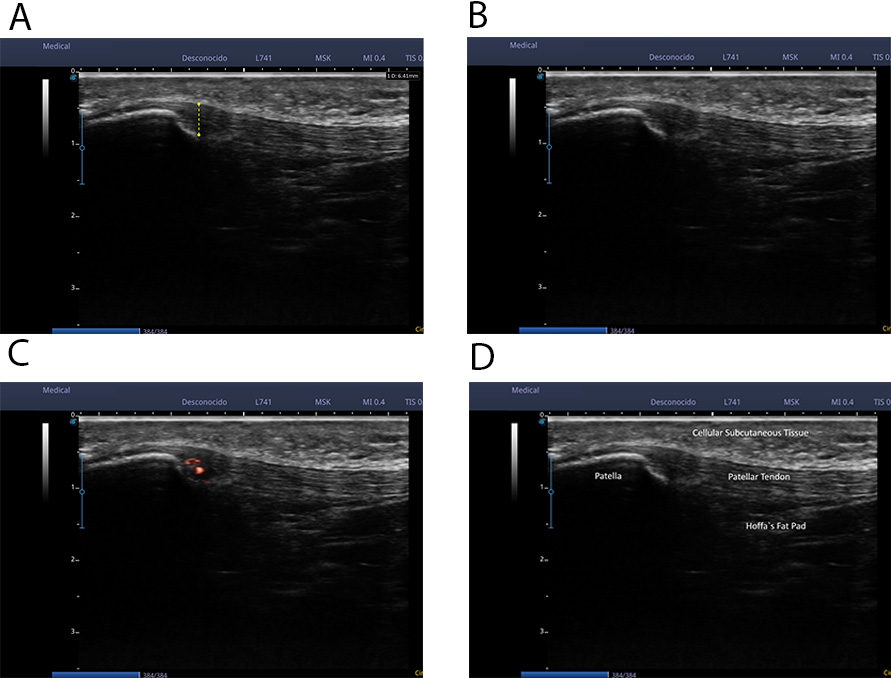

Three of the patients presented ultrasound images compatible with degenerative tendinopathy at the deep tendon interface in the area closest to the proximal insertion, as shown in Fig. 1A–C.

Fig. 1.Ultrasound images compatible with degenerative tendinopathy. (A) In the image we can observe an evident thickening of the patellar tendon in a longitudinal cut. (B) In the image we can appreciate a series of hypo-echoic images and tissue heterogeneity in the inner pole of the patella in a longitudinal cut. (C) In the image we can observe the presence of intratendinous neovascularization in a longitudinal cut. (D) Regional anatomy details.